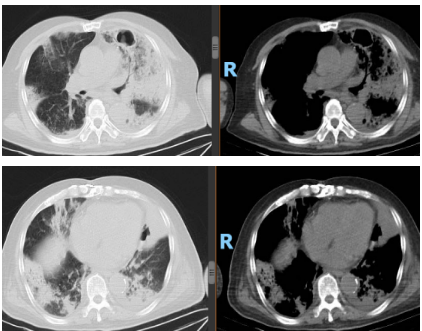

患者治疗10天后,复查炎症指标和胸部CT。

胸部CT复查结果: 双肺多发团片影,左肺内病灶可见空洞形成,双侧胸腔积液。

2025-10-31(入院27天后)复查

5. 复查血气分析(无创呼吸机辅助通气,S/T模式, IPAP 14cmH2O,EPAP 6cmH2O,氧浓度28%):PH 7.490,PCO2 40mmHg,PO2 61.2mmHg↓,SO2 93%,cK+ 3.36, cNa+ 141mmol/L,cCL- 104mmol/L,cLac 1.39mmol/L,cGlu 5.18mmol/L ,PaO2/FiO2 218.57mmHg↓↓↓。